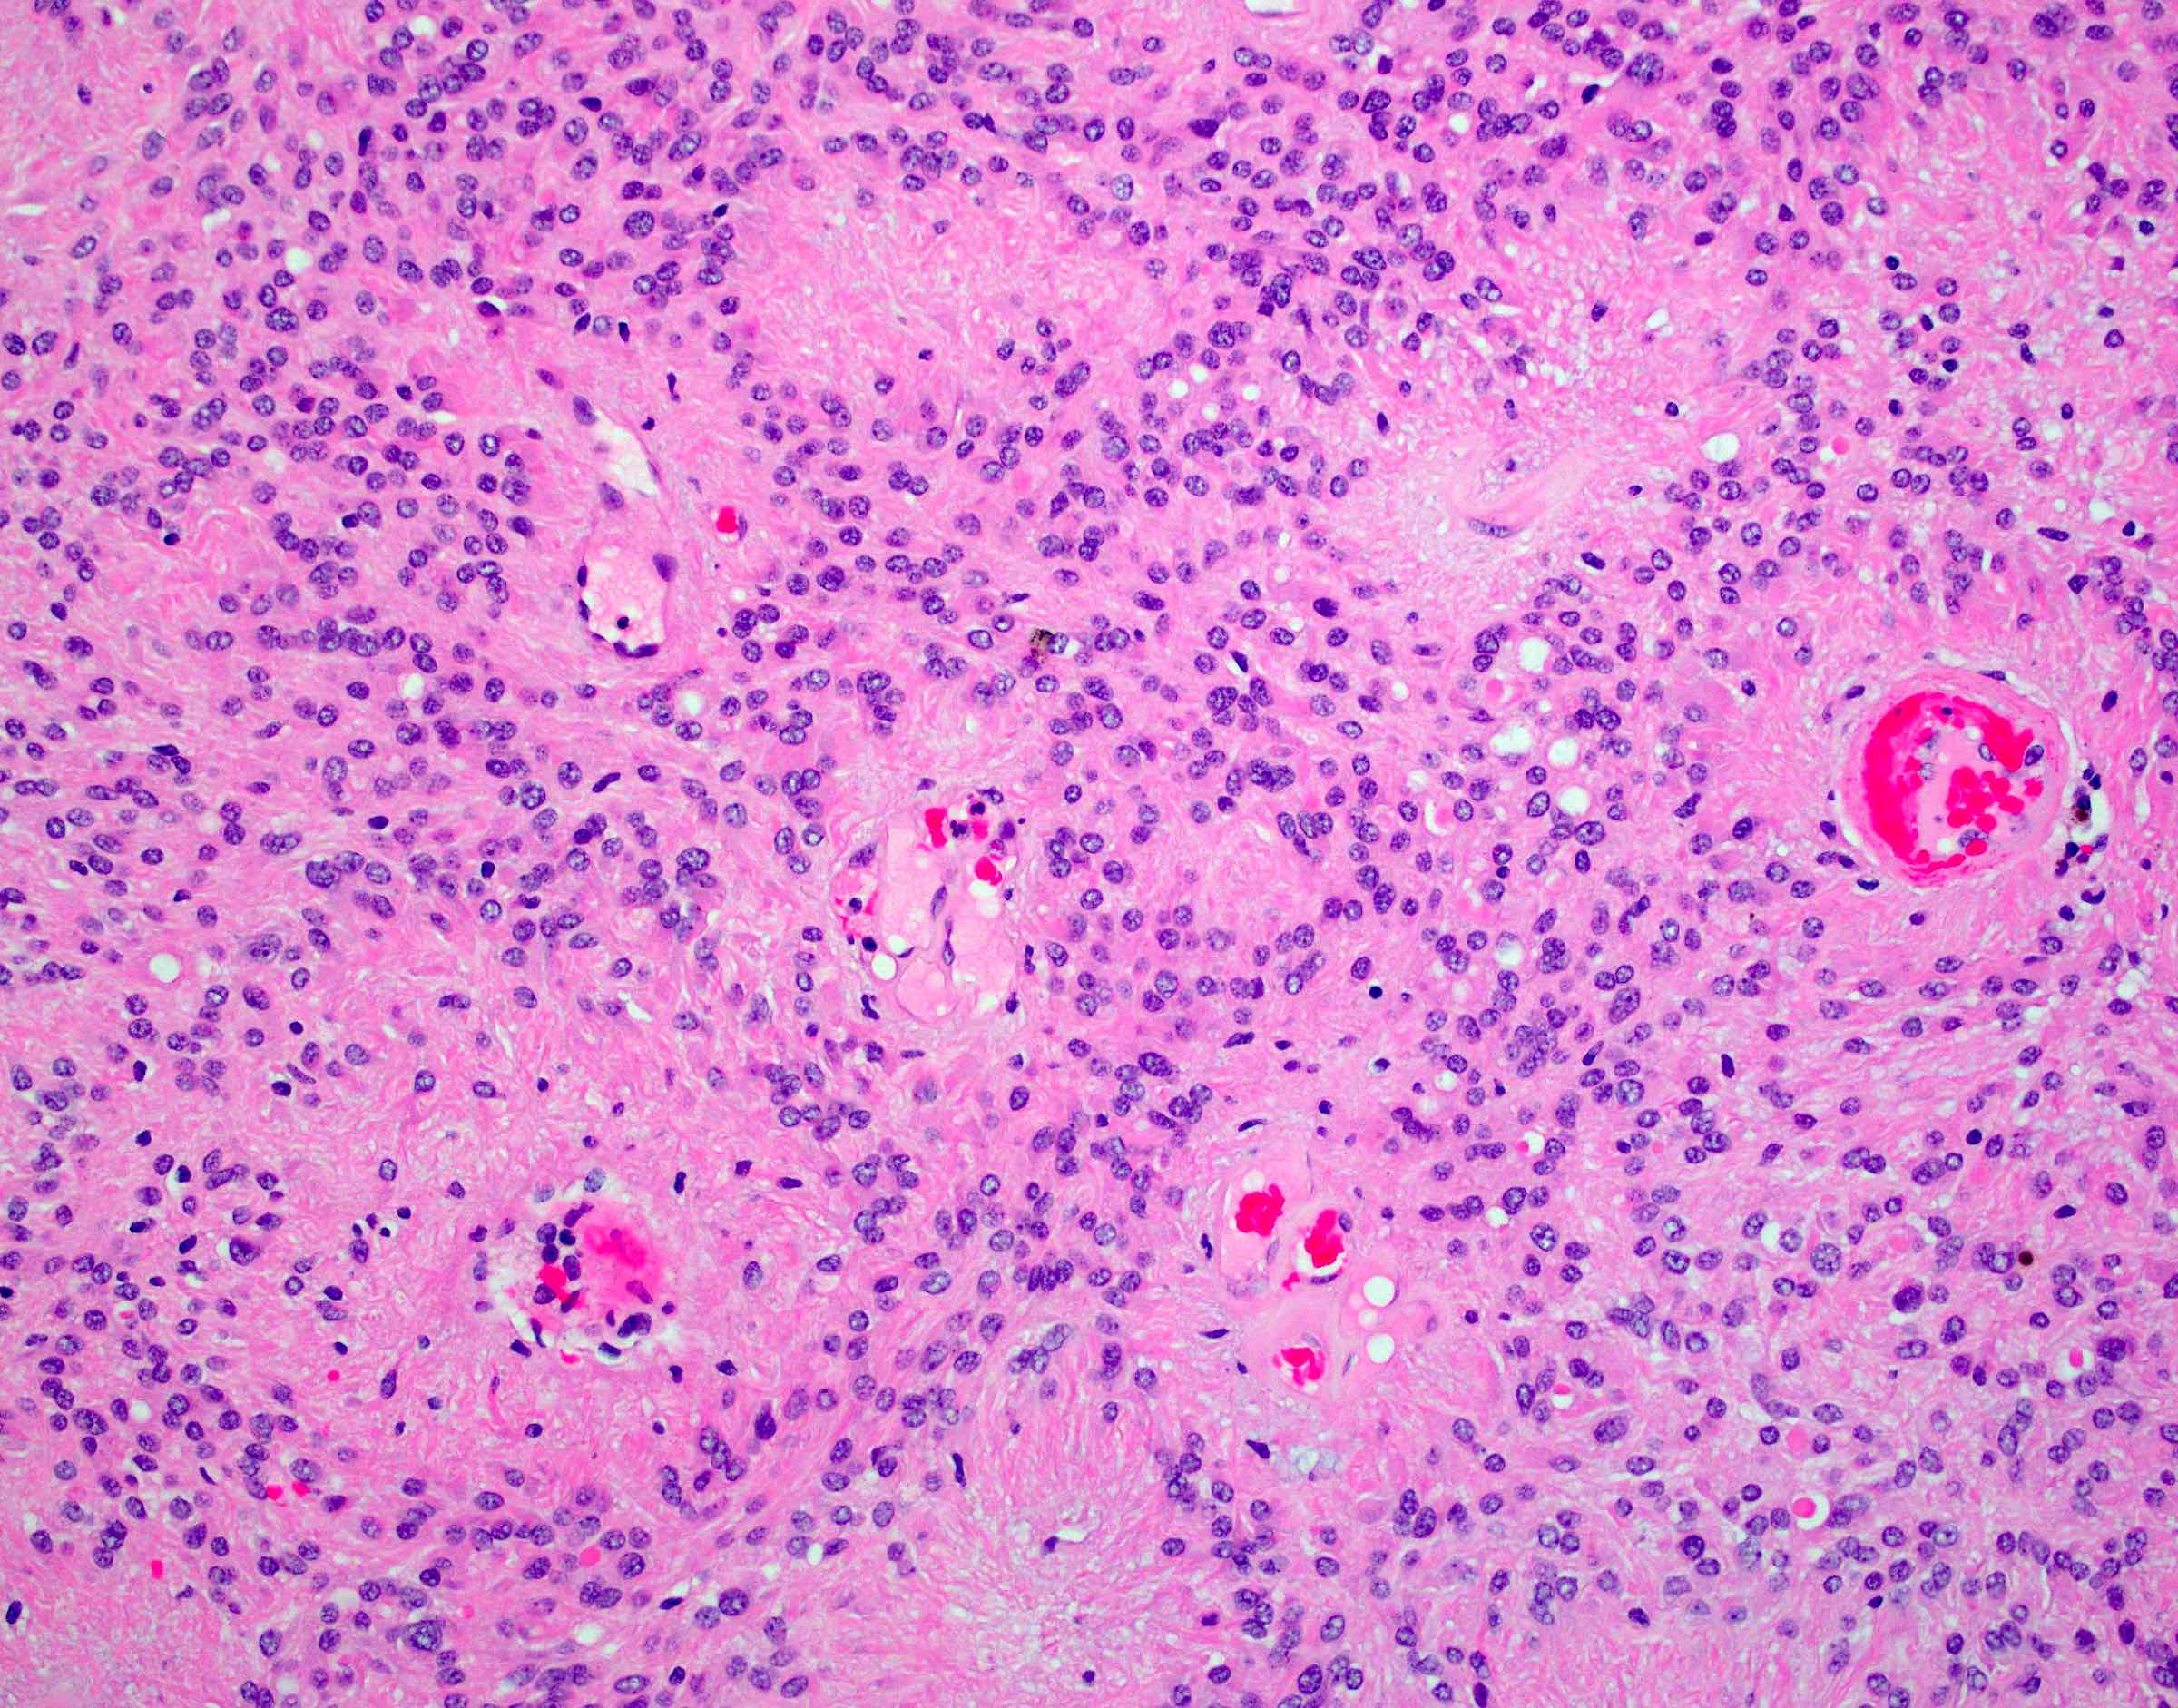

Microscopic (histologic) description

- Monomorphic round to oval cells with speckled chromatin

- Perivascular pseudorosettes, true ependymal rosettes, lumina and fibrillar areas

- Can have nonpalisading necrosis, areas of cystic or myxoid degeneration, calcifications, degenerative atypia, neuronal differentiation and rarely metaplastic elements

- Utility of histological grading is debated; the 2021 WHO still recommend assigning either WHO grade 2 or grade 3 to an ependymoma, according to its histopathological features as part of the integrated diagnosis

Microscopic (histologic) images